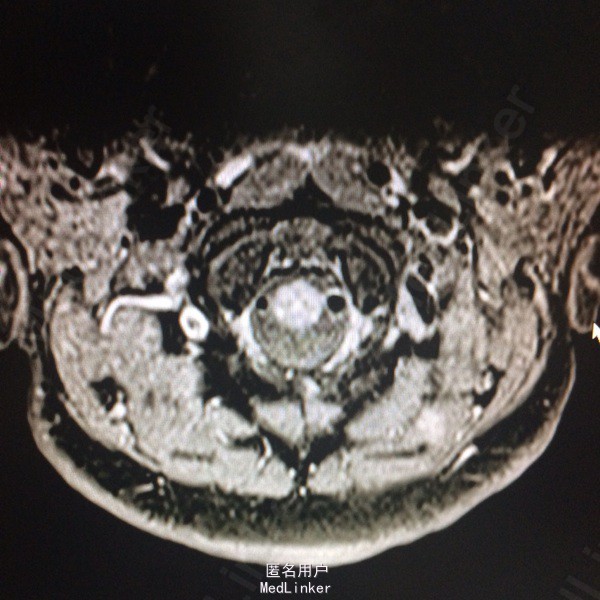

查体:左侧上肢、左侧颈项部、左侧躯干浅感觉减退,左上肢有力5-级,左侧肢体腱反射(+),余(-)。 辅助检查:头颅CT:右侧顶叶、左侧岛叶少许腔隙性梗塞,侧脑室旁脑白质变性,脑萎缩。 入院后查风湿三项:RF:74IU/ml,肌酣:92umol/L。尿酸:362umol/L,胆固醇:6.44mmol/L。糖耐量试验正常。输血四项正常。血沉、自免八项、血管炎3项、血找狼疮细胞均正常。心脏彩超正常。椎动脉彩超、颈动脉彩超正常。肌电图:左侧正中神经腕部节段性损害(感觉纤维受累,脱髓鞘改变),符合左侧腕管综合征电生理改变;左侧正中神经、左侧尺神经F波异常,提示近端神经根(C8-T1)受累,请结合临床。头颅MR:双侧额叶皮层下多发小缺血变性灶,未见急性梗死;右侧椎动脉颅内段较左侧明显细小,颅脑MRA未见异常;右侧桥小脑角增宽,未除蛛网膜囊肿。颈椎MR:颈椎轻度后弓,退行性变:C2/3、C3/4、C4/5、C5/6椎间盘突出(后正中型);C6/7椎间盘膨出,C1椎体水平脊髓内异常信号影,建议增强扫描。增强扫描示:C1水平脊髓内异常信号,脊髓炎与多发性硬化相鉴别。

诊断:急性脊髓炎。 治疗经过:入院后予B1、甲钴胺营养神经,患者症状稍有好转,在完善颈椎MR后考虑急性脊髓炎,予激素冲击治疗。